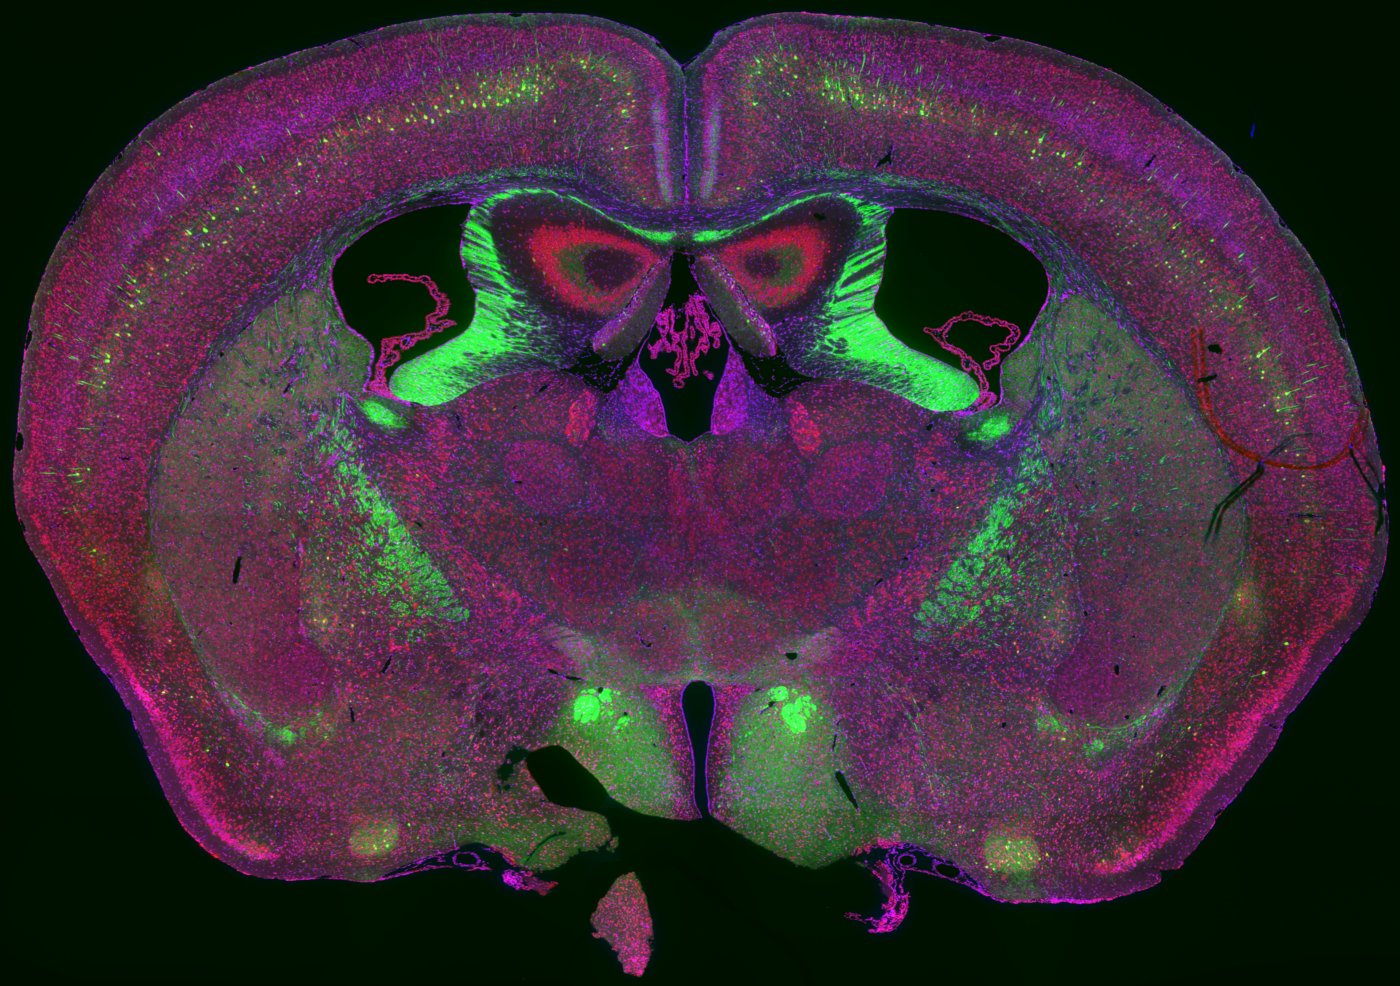

得益于世界各国对于脑科学研究的大力支持,伴随着半导体、光学、生物学、化学、计算科学与技术的发展,脑图谱相关技术得到了快速的发展,人类距离揭示大脑的结构奥秘越来越近。我们结合组织器官透明化技术及全脑高分辨荧光成像,研发了一系列高通量全脑成像技术,可以获得大脑及其它器官的完整三维全景图像,清晰呈现其全部细胞结构。

使用我们的技术可以采集到猕猴大脑的全景三维图像,这是目前为止独一无二的高精度灵长类大脑结构图像,原始图像数据量750TB,论文已经上传到bioRxiv预印本 。